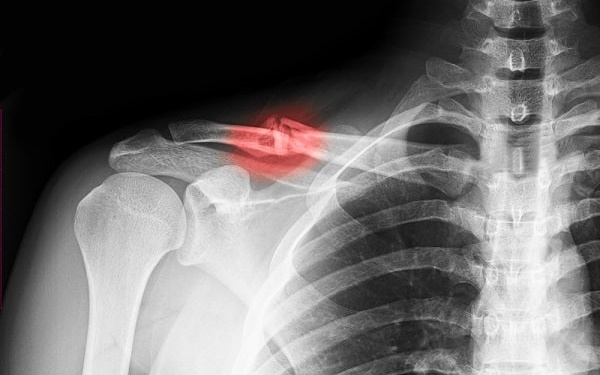

Sau khi xương gãy và liền lại, có thể xảy ra hai trường hợp: Xương liền ở vị trí như giải phẫu ban đầu hoặc xương liền lệch. Để đánh giá mức độ can lệch, cần thực hiện một cuộc kiểm tra lâm sàng kỹ lưỡng và sử dụng các phương pháp chẩn đoán hình ảnh như cắt lớp vi tính hoặc X-quang toàn trục chân. Nếu can lệch chỉ gây ít ảnh hưởng đến chức năng vận động, thì không cần can thiệp. Tuy nhiên, nếu can lệch nặng, có thể cần phải thực hiện phẫu thuật để điều chỉnh lại trục xương. Trong quá trình phẫu thuật này, thường sẽ cần phải đục bỏ phần xương đã gãy và liền lại, sau đó kết hợp xương lại theo đúng vị trí mong muốn.

Sau khi đến cơ sở y tế thăm khám và chụp X-quang, kết quả cho thấy rằng bệnh nhân bị gãy đầu dưới xương quay, và có sự di lệch và can lệch. Bác sĩ quyết định điều trị phẫu thuật gãy xương sau can lệch. Sau phẫu thuật, bệnh nhân được tập vận động và phục hồi chức năng sớm. Cẳng và bàn tay của bệnh nhân được phục hồi các chức năng gấp - duỗi.